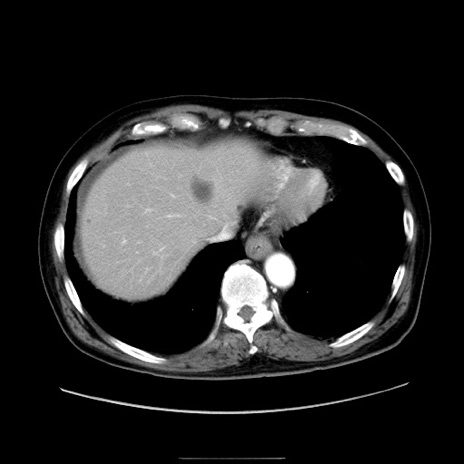

冠状断像

【症例】80歳代男性

【現病歴】約6時間前から臍下部痛が出現。次第に腹部膨隆・背部痛も生じてきたため来院。背部痛の場所は変化しない。

【身体所見】意識清明、BT 36.3℃、BP  131/87mmHg、P 87bpm、SpO2 100%(RA)、臍周囲自発痛・圧痛あり、反跳痛なし、自発痛部位に一致して板状硬あり、腹部膨隆、腸雑音減弱、CVA tenderness両側陰性。

【データ】WBC 19600、CRP 0.33